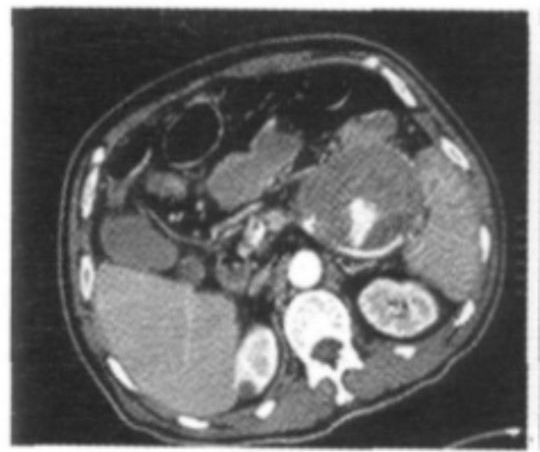

查体:心率90次/min,血压100/70mmHg,神志清楚,贫血貌,腹部平软,全腹部无压痛及反跳痛,肝脾肋下未触及。入院后血常规血红蛋白(HGB)84g/L;入院12h后再次发生新鲜血便,共5次,共500ml。心率升至124次/min,血压110/75mmHg。图1 腹部增强 CT。

诊断疾病胰腺假囊肿结肠瘘便血下消化道出血1、入院后保守治疗:积极抢救,给予输红细胞悬液、止血、扩容等治疗,改善一般状态。2、手术治疗:急诊于手术室中行肠镜检查,于横结肠近结肠脾曲见大量血凝块堵塞肠腔,内镜无法通过,未见明确出血位置。后急诊行DSA检查,未见明确出血病灶。急诊行腹部增强CT(图1),结果回报:考虑慢性胰腺炎并胰体尾部假囊肿,该病变侵蚀脾动脉并脾动脉瘘,与结肠脾曲关系密切,考虑存在该病变与结肠脾曲瘘。遂行手术止血。术中见胰体尾部假囊肿,该病变侵蚀脾动脉并脾动脉瘘,且与结肠脾曲瘘,导致下消化道出血,术中行脾切除、胰体尾切除、结肠脾曲切除肠吻合术。术后病理回报示:〔腹腔〕(胰腺体尾部)慢性胰腺炎,伴假性囊肿;(结肠脾曲)慢性溃疡,多灶性,局部穿孔,穿孔处与胰腺假性囊肿相通。3、术后行呼吸机辅助治疗,20d后痊愈出院。